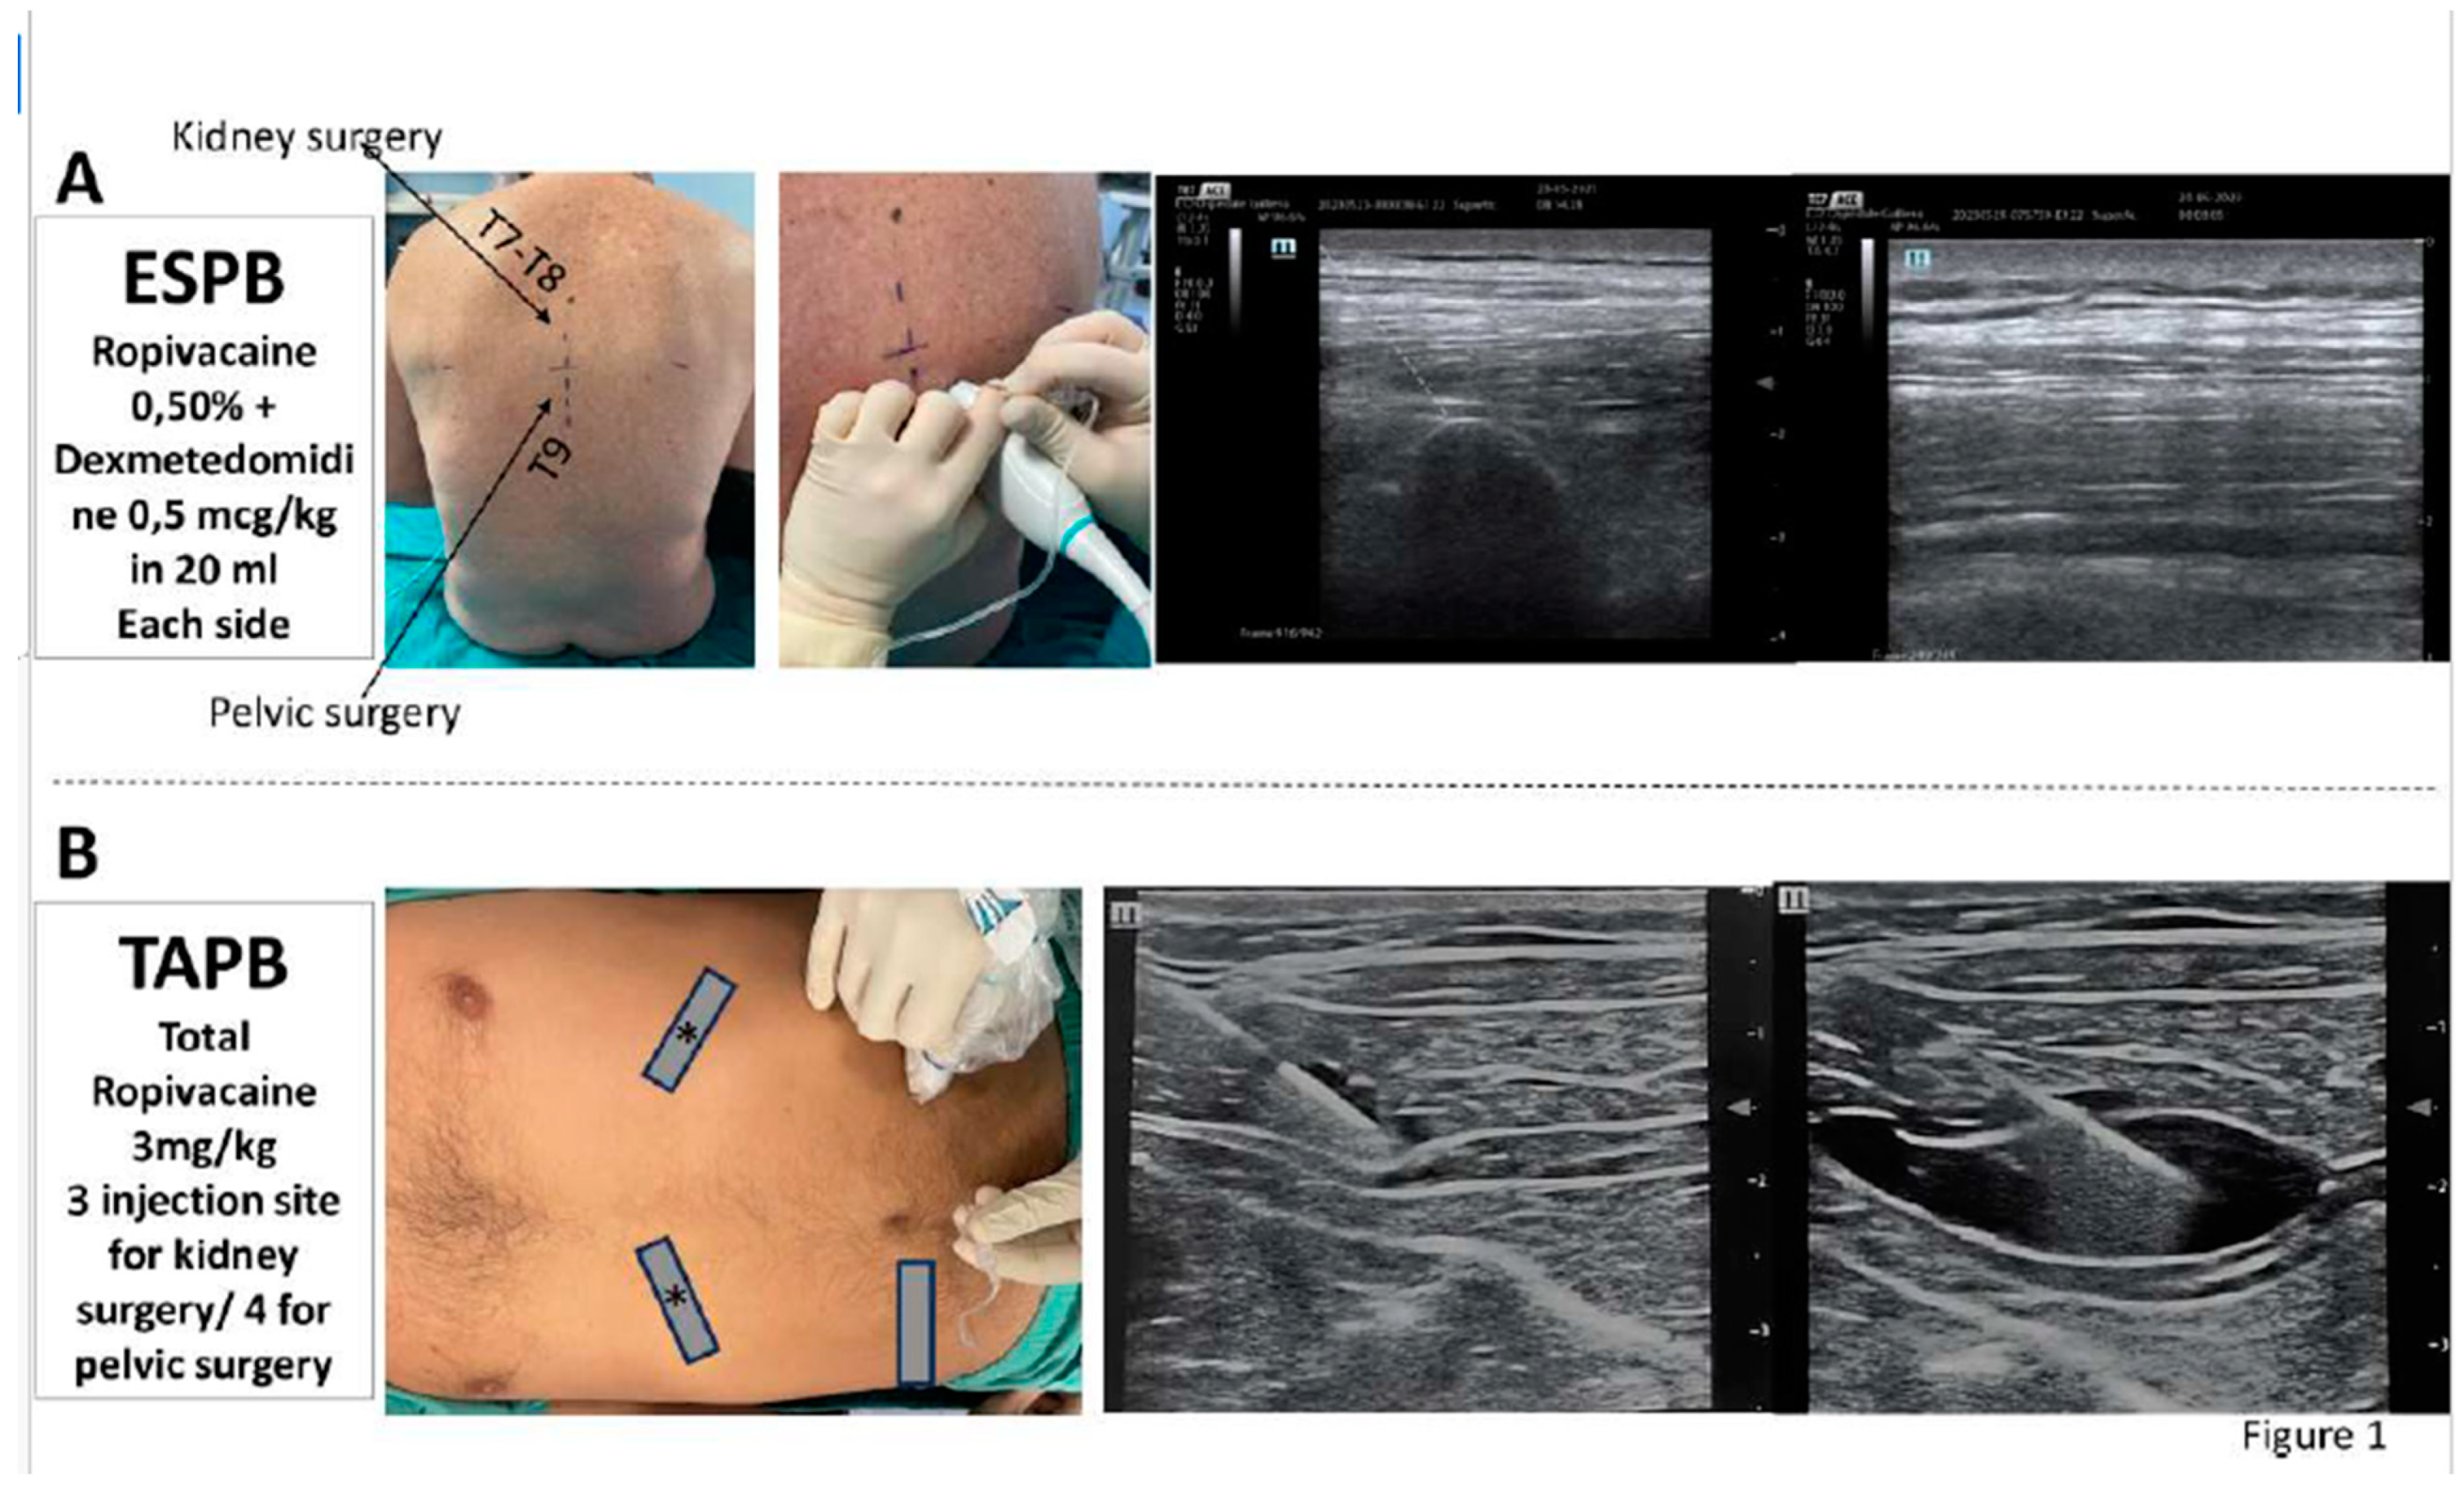

ESPB

TAPB